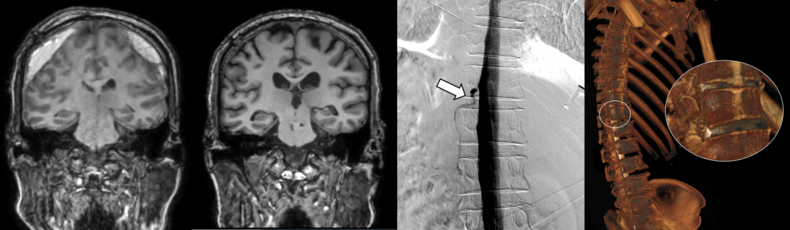

세브란스병원은 최근 DSM을 국내 최초로 도입해 이와 같은 기존 진단법의 한계를 극복했다. DSM(Digital Subtraction Myelography, 디지털 감산 척수조영술)은 척수에 조영제를 주입하고 모니터 화면으로 뇌척수액의 흐름을 실시간으로 확인할 수 있다. 이를 통해 뇌척수액이 새나가는 구멍을 정확하게 찾아낼 수 있게 됐다.

DSM과 더불어 세브란스병원이 함께 진행 중인 측위 CT 척수 조영술까지, 모두 뇌척수액 정맥 누공을 진단할 수 있는 최신 기법이다.

이번에 세브란스병원을 찾은 환자들은 DSM 검사와 측위 CT 척수 조영술로 뇌척수가 새어나가는 부위를 정확히 진단‧치료받고, 뇌압을 회복했으며 경막하출혈도 사라졌다. 이에 따라 환자들이 보였던 인지기능 저하와 보행장애도 모두 호전됐다.

하우석 교수는 “자발성 두개내압 저하증과 특별한 외상이 없이 발생하는 경막하출혈의 원인 중 하나였던 뇌척수액 척수 누공은 두통, 인지능력 저하 등 심각한 고통을 일으키지만, 기존 진단법으로는 원인 규명이 쉽지 않던 상황”이라며 “세브란스병원이 도입한 DSM과 측위 CT 척수 조영술로는 척수액 누출이 발생하는 지점을 정확히 찾아내 치료할 수 있다”고 말했다.